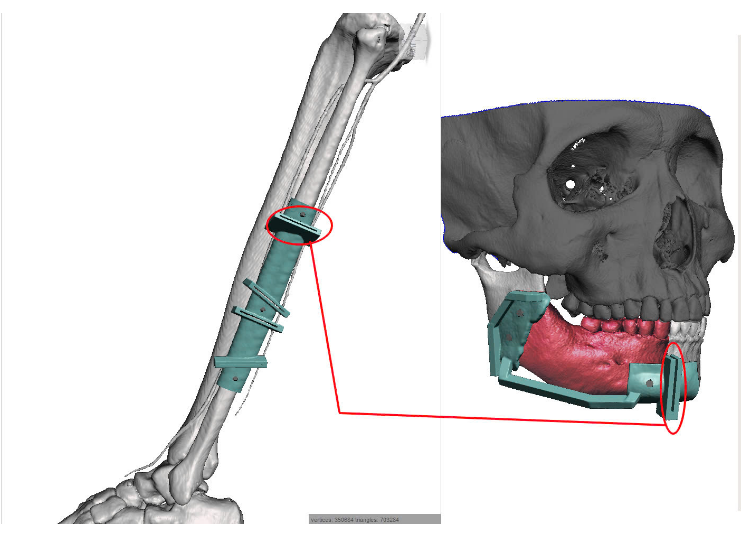

Để tối ưu hóa kết quả điều trị, công nghệ in 3D đã được ứng dụng trong toàn bộ quy trình từ thiết kế giả lập đến lập kế hoạch phẫu thuật. Công nghệ này cho phép thiết kế chính xác máng cắt xương và nẹp tái tạo, tạo mẫu hàm và máng hướng dẫn phẫu thuật với độ chính xác cao, đảm bảo quy trình thực hiện hiệu quả, an toàn và tối ưu hóa kết quả điều trị.

Bệnh nhân được phẫu thuật cắt đoạn xương hàm dưới, loại bỏ khối u với lề cắt an toàn 1cm, đồng thời tái tạo xương hàm dưới bằng vạt da cơ xương mác tự do. Đây là một kỹ thuật phức tạp, yêu cầu sự điêu luyện, tỉ mỉ và sức bền từ êkip phẫu thuật. Tuy nhiên, phương pháp này được hỗ trợ bởi công nghệ 3D, giúp các bác sĩ mô phỏng chính xác từng thao tác cắt, ghép và tái tạo. Nhờ đó, kết quả phẫu thuật được tối ưu hóa về cả mặt chức năng và thẩm mỹ, mang lại sự hiệu quả vượt trội cho bệnh nhân.

Quá trình thực hiện bao gồm: Bệnh nhân được thiết kế đường cắt và máng hướng dẫn phẫu thuật để cắt xương hàm và cắt xương mác (cutting guide) trên phần mềm, in máng, in mẫu hàm 3D sau khi đã giả lập cắt xương và tái tạo lại. Bẻ nẹp theo mẫu hàm giả lập trước. Sau đó, cắt đoạn xương hàm dưới từ cành cao đến phía xa răng 42, vạt da cơ xương mác sau khi phẫu tích sẽ được cắt theo cutting guide. Kết hợp xương mác vào nẹp tái tạo đã uốn sẵn, sau đó kết phức hợp vạt, nẹp vào xương hàm dưới bảo đảm khớp cắn và khản năng vận động của xương hàm. Cuối cùng là kỹ thuật vi phẫu khâu nối mạch máu đảm bảo sự sống của vạt tái tạo.

Xương hàm dưới không chỉ đóng vai trò quan trọng trong chức năng ăn nhai, nói, nuốt mà còn định hình cấu trúc khuôn mặt. Do đó, việc tái tạo lại các khuyết hổng lớn sau phẫu thuật luôn là ưu tiên hàng đầu. Vạt xương mác tự do với công nghệ in 3D mang lại nhiều ưu điểm: Đảm bảo cung cấp đủ xương cho tái tạo các đoạn lớn, cho phép thực hiện đồng thời hai kíp mổ nhằm rút ngắn thời gian phẫu thuật đồng thời tăng độ chính xác và hiệu quả trong điều trị.

Bác sĩ Đỗ Văn Tú – Khoa Mặt Hàm, Bệnh viện Quân y 175, người trực tiếp phẫu thuật, cho biết: “Ứng dụng phần mềm tạo “ cutting guide” và in mẫu hàm giúp phẫu thuật viên có đường cắt chính xác nhất, đặc biệt giúp tạo ra xương hàm dưới từ xương mác hoàn hảo nhất dưới mọi góc độ. Việc tính toán chi tiết các đoạn cắt, ghép sẽ giúp các bác sĩ thực hiện phẫu thuật một cách đơn giản và chính xác, thay vì phải chờ đợi đến khi bệnh nhân lên bàn mổ mới thực hiện các tính toán mất nhiều thời gian như trước đây. Lập kế hoạch và thực hiện đúng theo kế hoạch khi ứng dụng công nghệ 3D trong vi phẫu là yếu tố quan trọng để đảm bảo kết quả tối ưu về thẩm mỹ và chức năng cho bệnh nhân.”